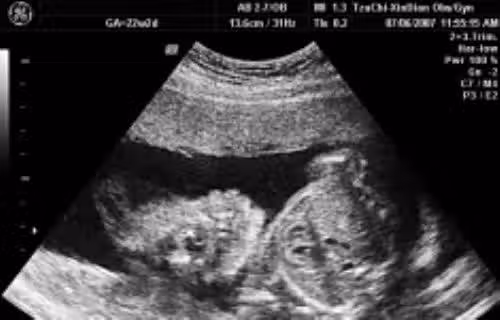

高二的女兒「不小心懷孕」,而且因為藏肚看不出來,直到8個月大才發現,但爸爸選擇不責備,親吐真心話「不敢讓妳知道爸爸心痛」😭😭 #最後處理方式讓人鼻酸

示意圖來源:噓星聞、媽媽經